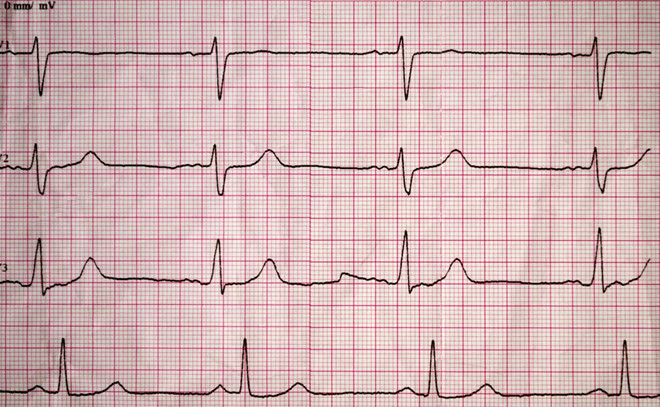

Bệnh tim mạch

Hai bệnh tim mạch phổ biến là mạch vành và suy tim, có liên quan tới các vấn đề về giấc ngủ. Trong bệnh mạch vành, sự thay đổi nhịp sinh học có thể dẫn đến cơn đau ngực, tim loạn nhịp, hoặc thậm chí là một cơn đau tim trong khi ngủ. Suy tim khiến lượng máu tim bơm đến các cơ quan trong cơ thể không đủ. Và kết quả là máu tích tụ lại xung quanh phổi khi bạn nằm, khiến bạn thức dậy vào nửa đêm. Sử dụng gối để nâng cao phần trên cơ thể lên có thể giúp bạn cảm thấy dễ chịu hơn.